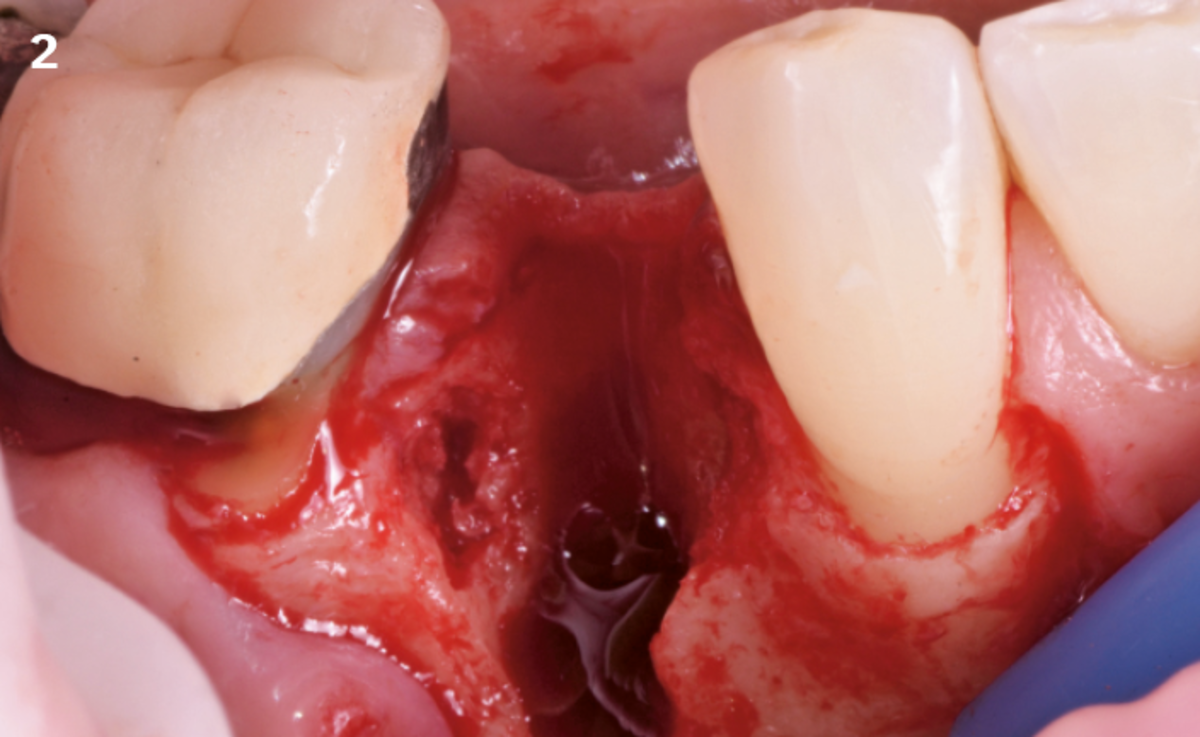

"After the extraction, I realized that the buccal wall was missing and I had to leave the membrane exposed. The regenerative potential of the site could be poor, so I decided to boost the biomaterials’ effect with polynucleotides and hyaluronic acid."

The Situation

The patient (45 years old, female, non-smoker, no previous pathologies) is referred for extraction of tooth 45 and immediate implant placement. The site showed an increased probing depth and a marked bone loss.